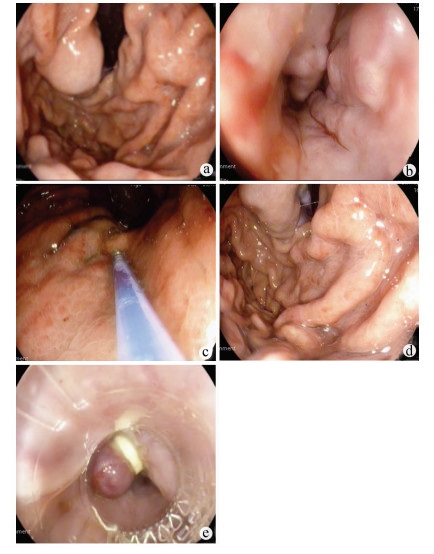

Endoscopic treatment of gastroesophageal varices complicated by posterior reversible encephalopathy syndrome: A case report

Tingting YU, Shanshan JIANG, Mengran ZHU, Yun BAI

2022, 38(1): 177-179. DOI: 10.3969/j.issn.1001-5256.2022.01.030

Abstract(830) HTML (198) PDF (3069KB)(60)

Abstract: